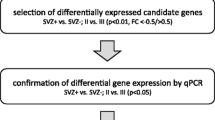

For methylome analysis, idat files were processed with the minfi R package [8, 18]. Data were filtered for probes mapping to chromosome X and Y, as well as single nucleotide polymorphisms (SNPs) and repetitive sequences. Data were funnorm normalized, and M-values were used for analysis. Identification of differentially methylated CpGs between SVZ+ and SVZ– tumors is outlined in Suppl. Figure 1, online resource.

The MRI classification was utilized to identify the most relevant differentially methylated probes (DMP, 225 CpGs, defined with p < 0.001) using Illumina 450 K microarrays. Hierarchical clustering (HCL) for identification of the least stable classification error between the two modalities and the most relevant DMP among these 188 CpGs were selected by random forest analysis (details in Suppl. Figure 1, online resource). This analysis resulted in a 15 CpG DNA methylation signature distinguishing between SVZ+ and SVZ– tumors (SVZM, Fig. 1B, Suppl, Fig. 11, online resource, upper row). This separation was also seen on global epigenetic level (non-selected CpGs, Suppl. Figure 11, online resource, bottom row). Among the selected CpGs, 5 of the 15 DMP were associated with the LRBA gene. Heatmap and HCL of the SVZM classified training cohort combined with other relevant parameters (i.e., MRI evaluation, IDH1, CIMP, and MGMT status) are provided in Fig. 1C. SVZM clearly separated the training cohort into prognostic subgroups (p = 0.003, LRT). No enrichment of SVZ assigned tumors to previously discovered glioma methylation subtypes was found based on hierarchical cluster analysis of most variant probes (Suppl. Figure 2, online resource), using the v11b4 neuropathology classifier [13] revealed that all subtypes were present in SVZM+ and negative tumors (Suppl. Figure 2C, online resource). A previously observed trend between MRI classification and degree of resection (p = 0.08, chi-squared test) was weaker for SVZM (p = 0.26, Suppl. Figure 3A, online resource). In concordance, Goodman Kruskal’s lambda showed smaller values for SVZM, however the 95% CI included 0 (no association) for all performed comparisons (Suppl. Figure 3A, online resource). Finally, multivariable survival analysis of the extent of resection and SVZ classification method did not show a significant contribution of adding the extent of resection in either case (SVZM: p = 0.47 and MRI: p = 0.43, Suppl. Figure 3B, online resource).

Segmental CNV alterations revealed loss of chromosome 10 in SVZM– tumors and gains on chromosome 19 in SVZM– tumors (Fig. 4A). Segmental and gene/transcript level CNVs are shown in Suppl. Figure 6A and B, online resource. On whole exome sequencing data (WES, TCGA cohort), evaluation of variant calls from four pipelines revealed differentially enriched mutations mostly confined to SVZM– tumors (Fig. 4B), whereas the total number of non-silent mutations did not differ between the two classes (Suppl. Figure 7A, online resource). More specifically, frame shift deletions/insertions, in-frame deletions, mutations in splice regions, and splice sites were enriched in SVZM + tumors (Fig. 4D). EPHA1, DECAF12L2 and ADCY5 mutations were detected exclusively in SVZM + tumors, whereas CNTNAP2, AHNAK2 and ITIH6 mutations were among the most significantly enriched in SVZ– tumors (p < 0.01) (Fig. 4B). Deep panel sequencing of the Heidelberg cohort revealed no mutational enrichments as a function of SVZM classification; at 10% FDR for the exclusive presence of ARID1B1 and BRCA2 in SVZ+, and VHL in SVZM– tumors. Cross-comparison of mutational readouts between the Heidelberg and TCGA cohorts was limited by differences in methodology (e.g., sequencing depth and consequently VAF cut-off criteria applied to define mutations). Therefore, it was not surprising that repetitive elements difficult to detect with WES such as TERTp mutations were found in 46 (85%) samples of the Heidelberg cohort but not reported in the TCGA study (Fig. 4C). Accordingly, we failed to confirm an exclusive enrichment of mutations in SVZ+ tumors identified in the Heidelberg cohort with TCGA WES data (Suppl. Figure 7C, online resource).